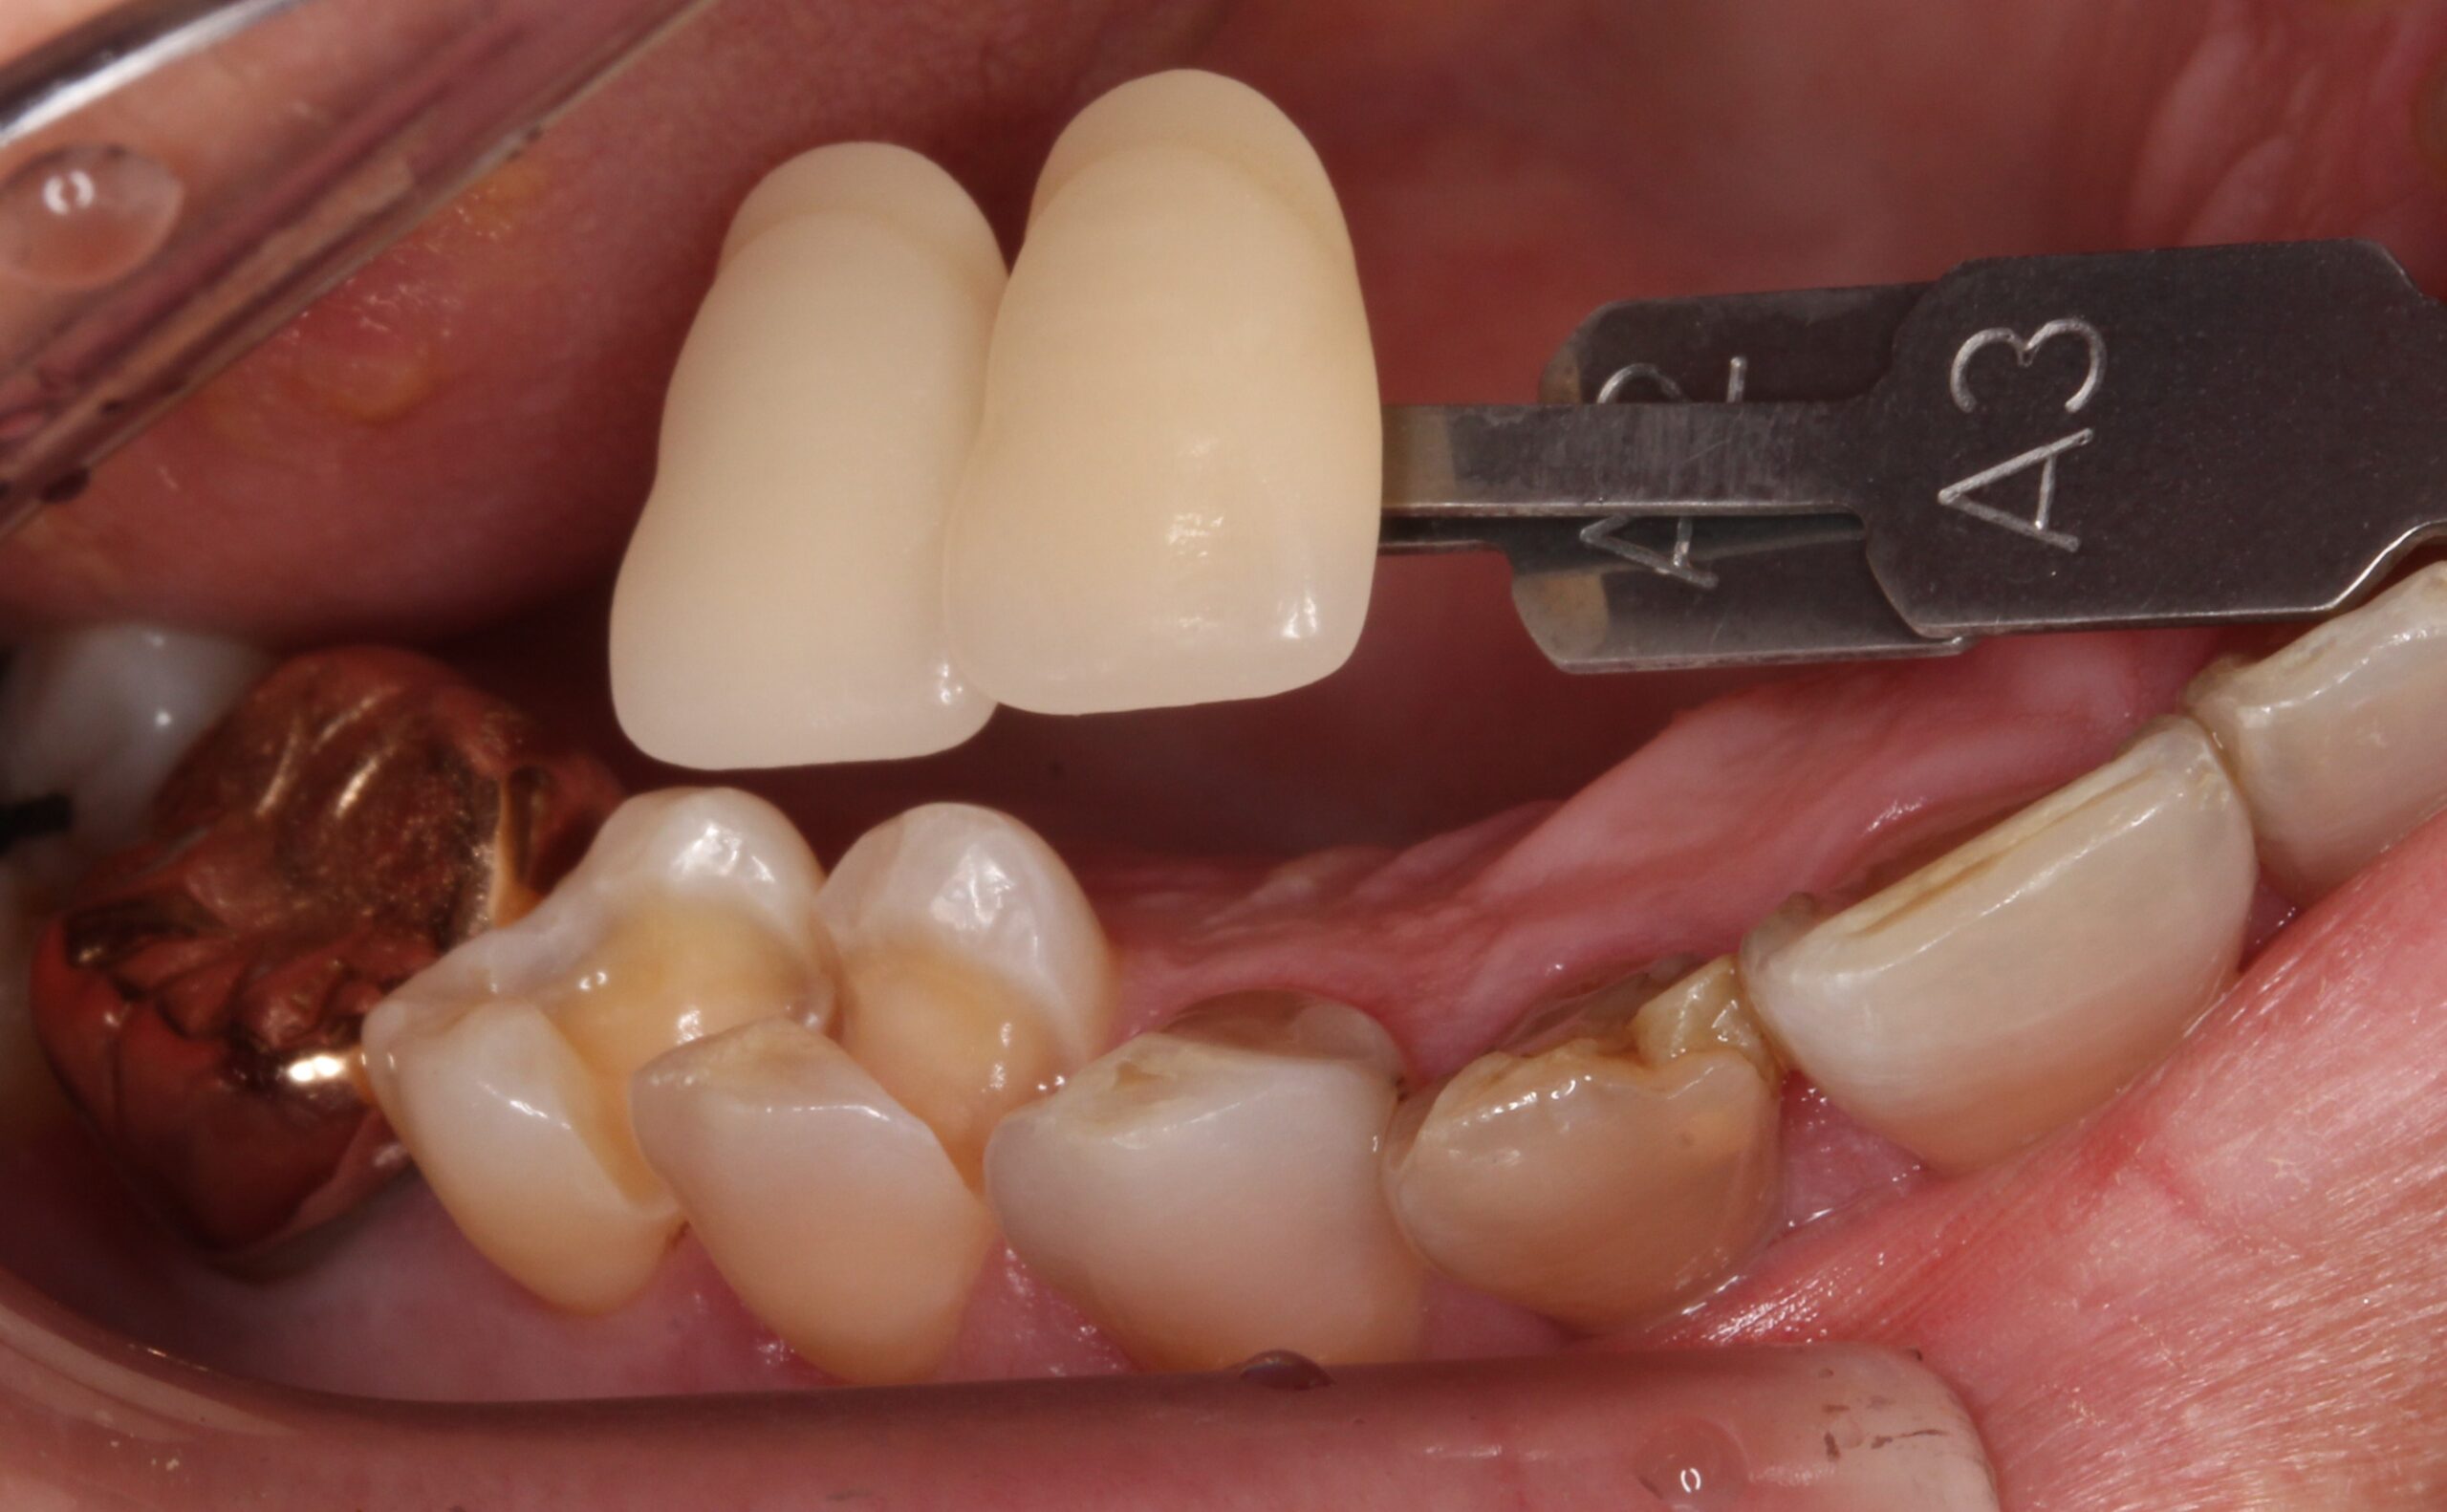

ゴールドインレー(金合金)が虫歯?その原因は?